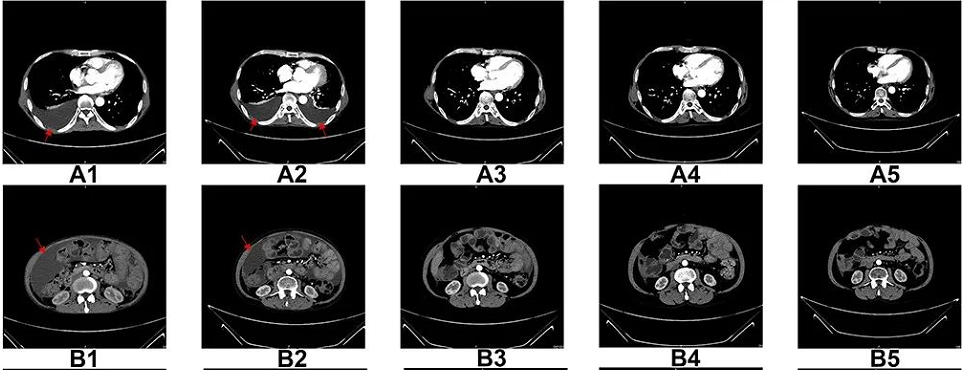

图A1-A5:CT扫描显示,6个疗程后胸腔积液完全消失;

图B1-B5:CT扫描显示,6个疗程后腹水几乎完全消失;